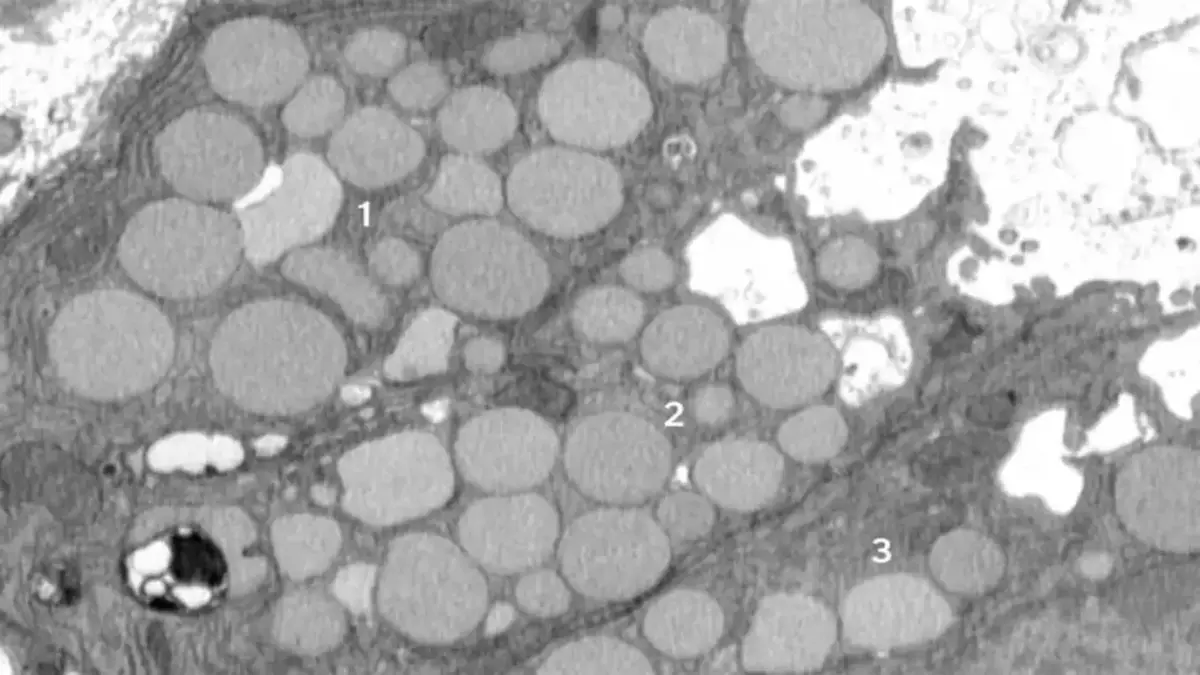

St. Louis, Amerika Serikat - Para peneliti dari Washington University dan Baylor College menemukan sebuah proses baru dalam sel yang membantu penyembuhan luka dengan cara berubah menjadi seperti sel induk. Proses ini dinamakan cathartocytosis, yang berarti sel mengeluarkan komponen lama dengan cara seperti 'muntah' agar bisa mulai memperbaiki diri dengan cepat.

Studi yang dilakukan pada tikus dengan luka di lambung tersebut menunjukkan bahwa ketika sel mengalami cedera, mereka akan melakukan pembersihan cepat terhadap bagian-bagian sel yang sudah tua dan rusak. Ini membuat sel bisa memperbarui diri dan memperbaiki jaringan lambung yang terluka secara lebih efisien.

Mekanisme cathartocytosis merupakan bagian dari proses yang lebih besar bernama paligenosis, di mana sel dewasa menjadi lebih ‘muda’ dan bersifat seperti sel stem yang mampu memperbanyak diri untuk mengganti sel yang rusak. Proses ini mirip dengan cara tubuh melakukan regenerasi jaringan, tetapi dengan cara yang lebih cepat.